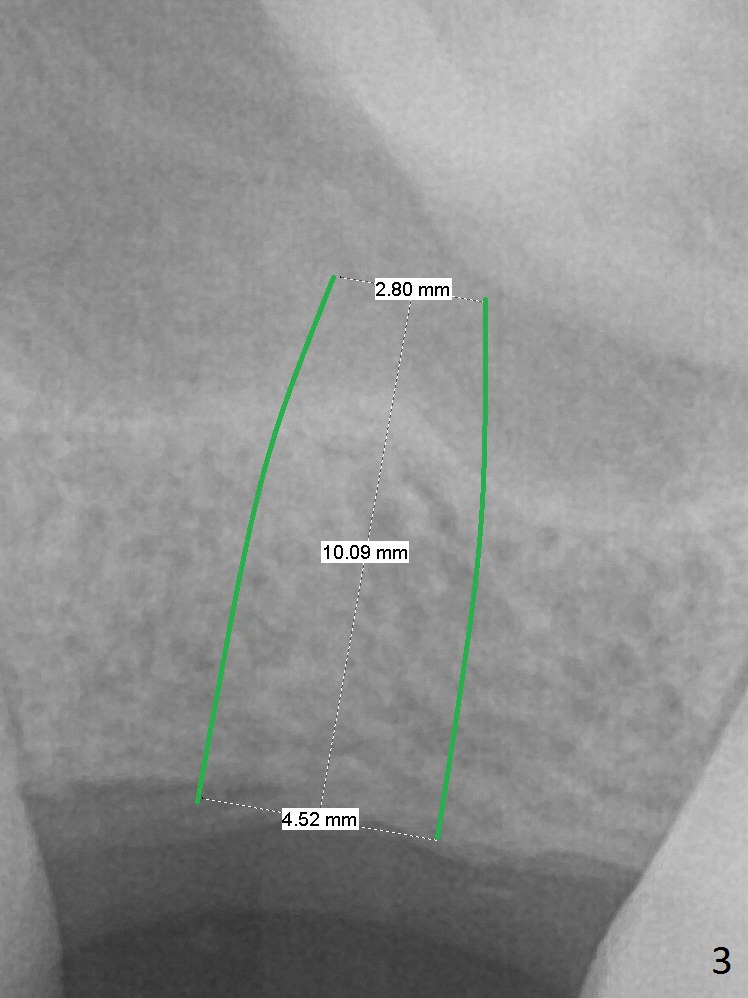

A 47-year-old man agrees implant at #14 (Fig.1).  He worries about the bone height.  There appear to be 2 layers of the sinus floor (Fig.1,2 (arrowheads: upper one)).  The horizontal plate of the palate is indicated by *.  An IBS implant will be placed between the 2 layers of the sinus floor as shown in Fig.3.  Osteotomy is initiated with Magic Split, followed by Magic Expanders (initial depth 9 mm gingival level) or Magic Lifter.  Before placing the implant, insert PRF and Allograft with a condenser with a stopper.